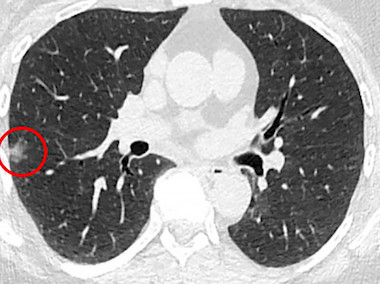

Cellvizio endoscopy could assist accurate discrimination during diagnosis of pulmonary nodules.

As proof-of-concept, the study evaluated NIR-nCLE for identification of malignant cells during biopsy of solitary pulmonary nodules (SPNs) from five patients. SPNs are the most common incidental nodule detected annually in the United States, according to the Abramson team.

Results showed that the NIR-CLE technology had the resolution to identify a single cancer cell among normal fibroblast cells when co-cultured at a ratio of 1:1000, and could detect cancer cells in human tumors less than 2 centimeters in diameter. The platform delivered easily interpretable images in real-time, an important consideration if accurate discrimination between tumor and normal tissue are to made by non-expert observers.